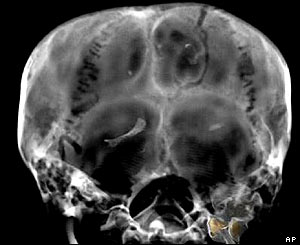

The scan provided some fascinating images of the boy pharaoh's body.

Researchers said results of the scan put paid to the theory that Tutankhamun was murdered.

One old theory was that a sliver of bone found in his head indicated that he had suffered a blow.